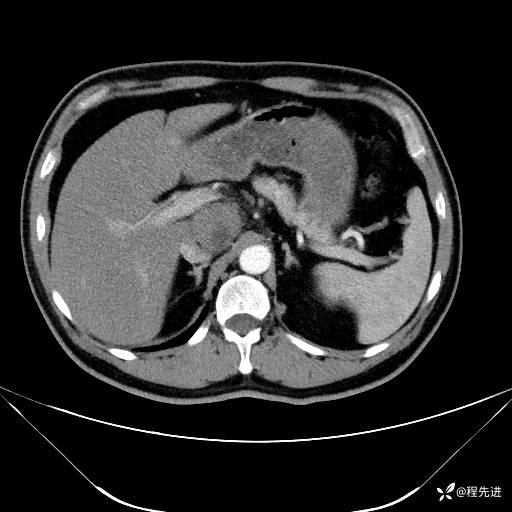

【腹盆】特别精彩病例|发现腹膜后肿物1月余

主诉:发现腹膜后肿物1月余

现病史:患者1月余前查体,行超声检查提示:后腹膜囊实性肿块;慢性胆囊炎伴胆囊内结石;无腹痛腹胀,不伴腹泻发热等;偶感腰背部酸痛。

CT平扫+增强: